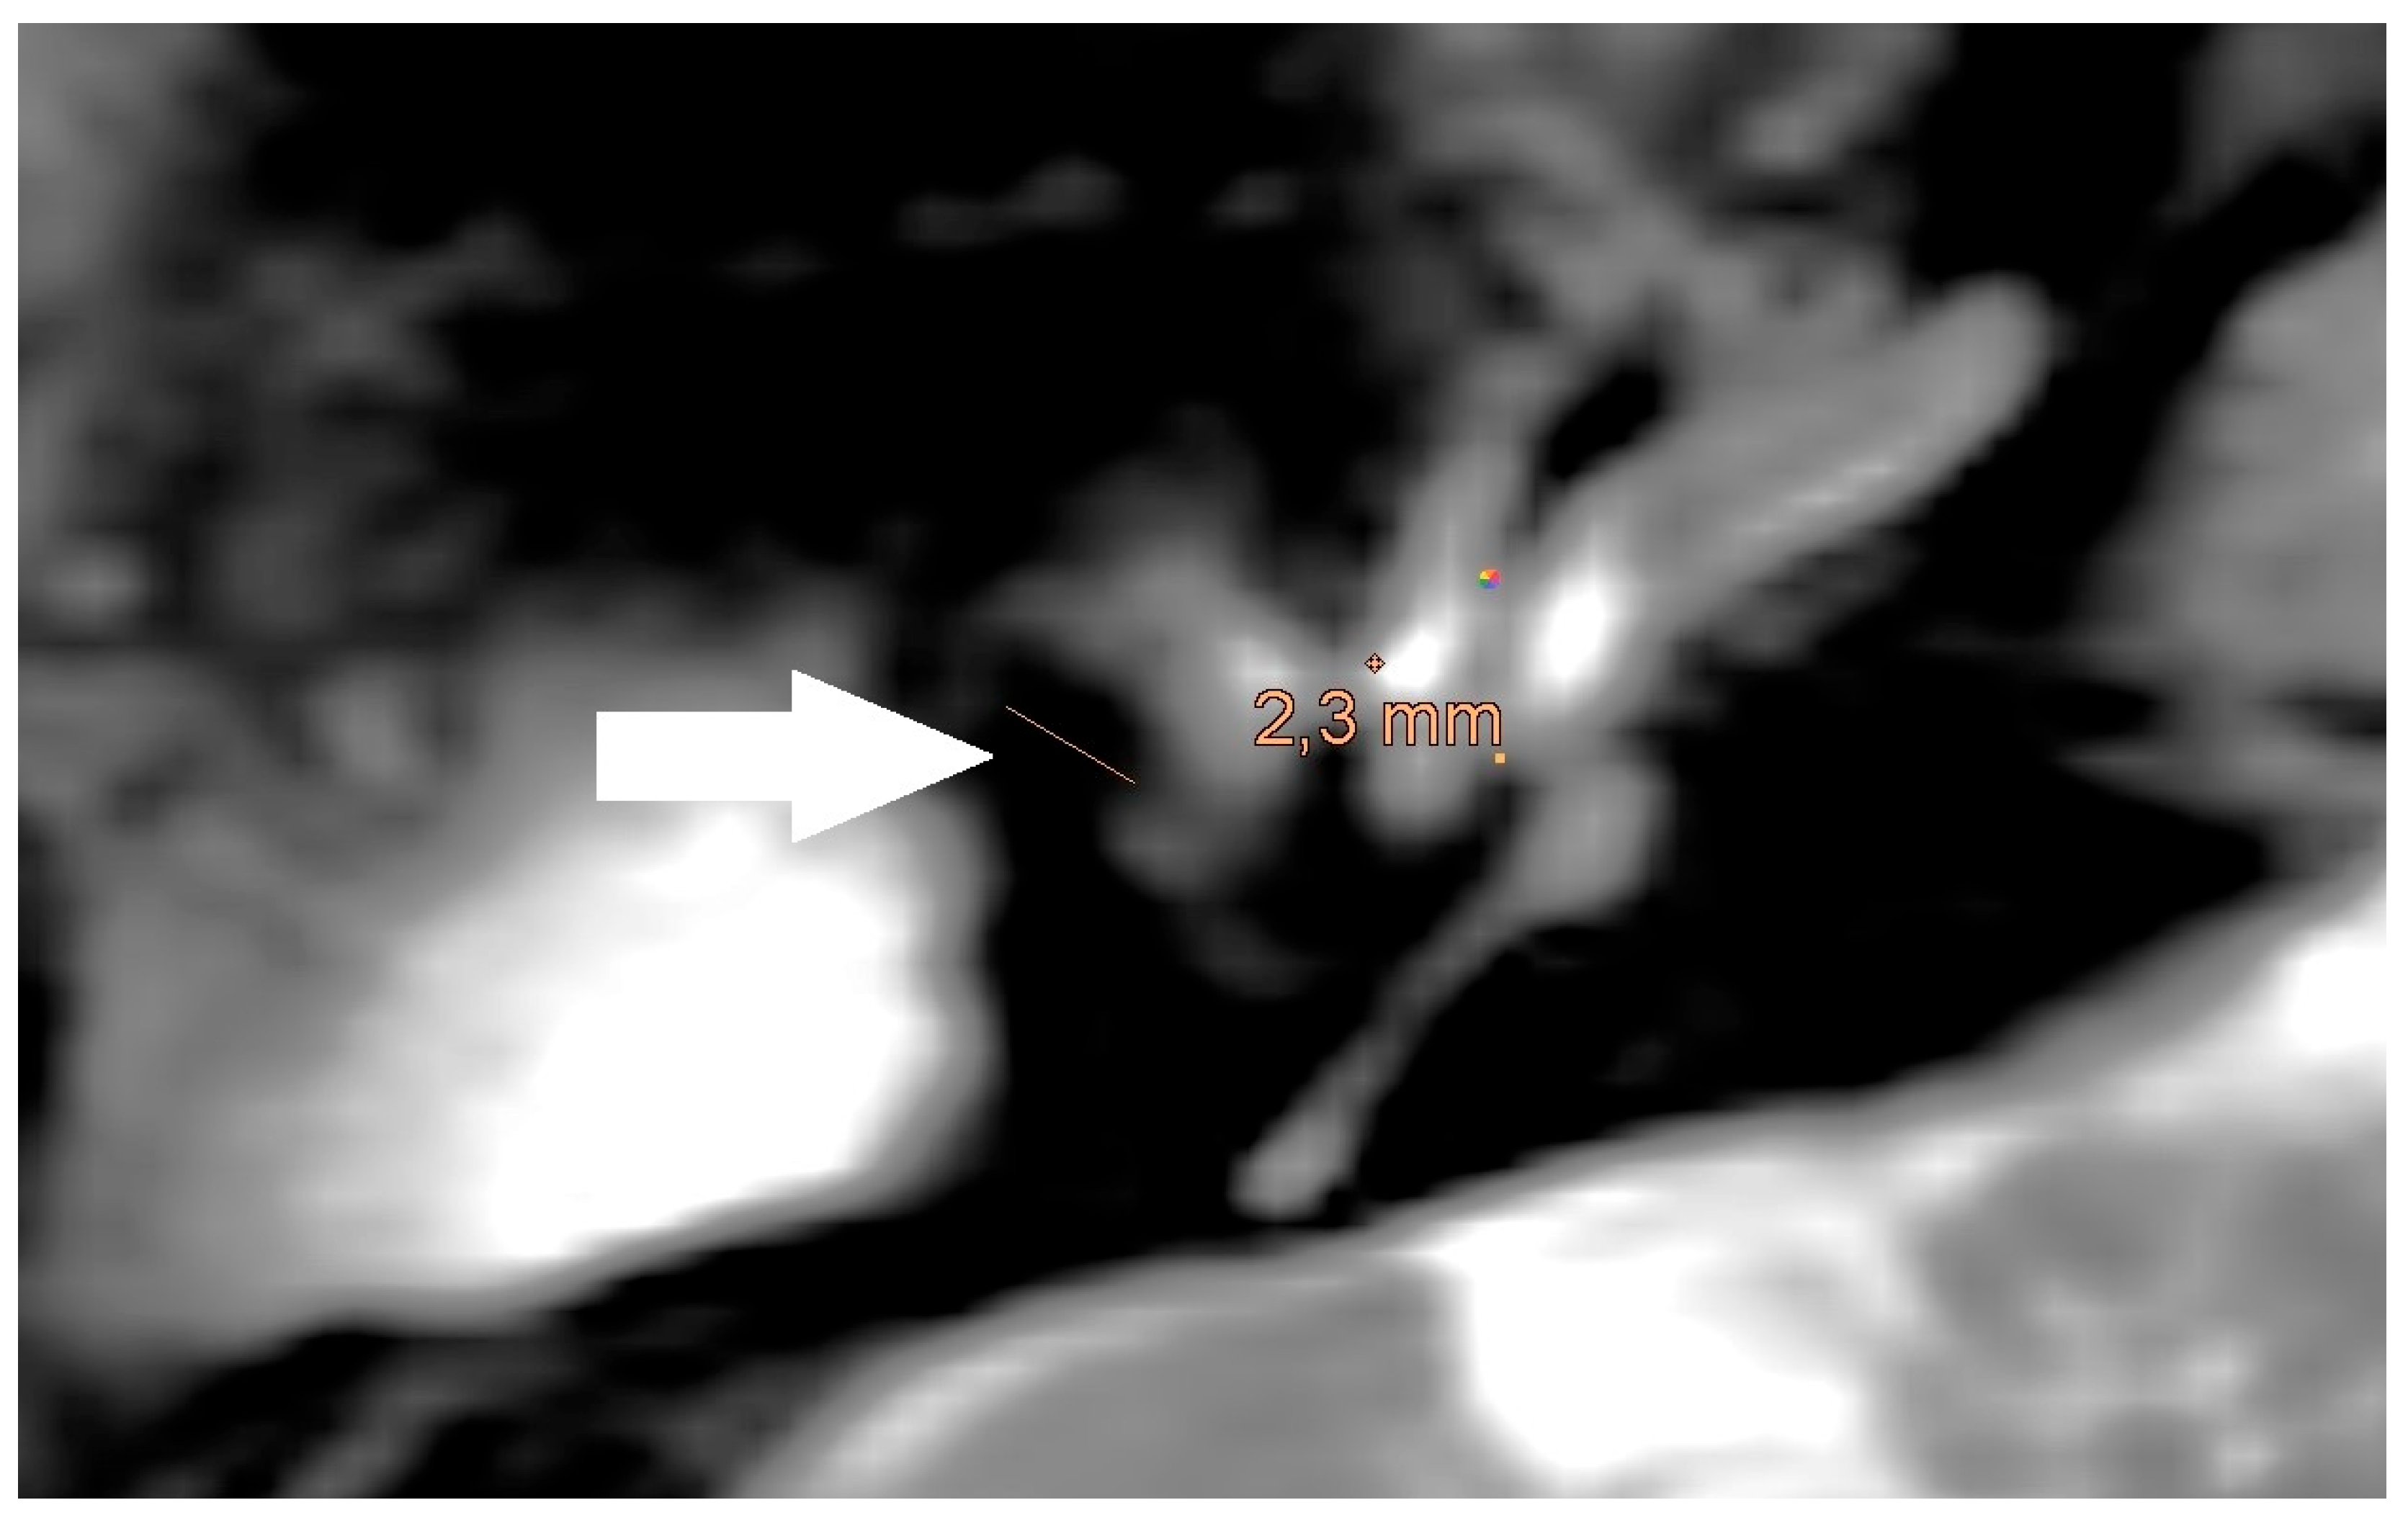

Figure 4. Magnification of the same artifact from Figure 1a with measurement (White arrow).

Figure 5. Magnification of the same artifact from Figure 1b with measurement, see white arrow.

The artifact measurements firstly done in T1- or T2-sequence showed an average artifact of 3,1 mm for PORP, 4,7 mm for TORP and 3,6 mm for meshes (see Figure 4, Figure 5 and Figure 6). The overall average artifact was 3,8 mm.

The detection rate of a cholesteatoma also depends on the presence of a prosthesis and the proximity of the cholesteatoma to the prosthesis. In our study, the prostheses cause artefacts of at least 2.2 mm in the T1-/T2 sequences. In the non-EPI DWI sequence, the voxel size is 1.9mm and larger than in T1-/T2 sequences. So, to detect a cholesteatoma the cholesteatoma must have a size of larger than 1.9 mm. A cholesteatoma smaller than 1.9 mm which is near to the prosthesis would be covered of the artifact of the prosthesis. Our findings are similar to former studies [18].